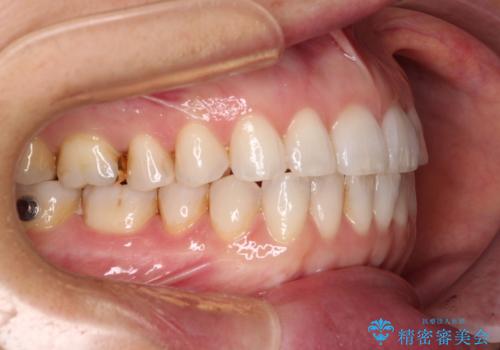

ちょっとしたデコボコをしっかりと改善したい インビザライン矯正

- 前歯のデコボコと上下スペースと前歯の隙間を気にして来院された患者様です。

目立たない装置を希望とのことでインビザラインにより、デコボコを解消しつつ、上下の前歯の隙間を閉じていくこととしました。

デコボコはあっという間に解消されましたが、上下前歯の隙間がなかなか解消されませんでした。

飲み込みの際に舌を前方に突出する癖があり、飲み込みの度に前歯に強く接触していたため、上下前歯の隙間が維持されていました。

舌の訓練を徹底していただいたことで、徐々に隙間は解消され、きれいな歯列に整えることができました。